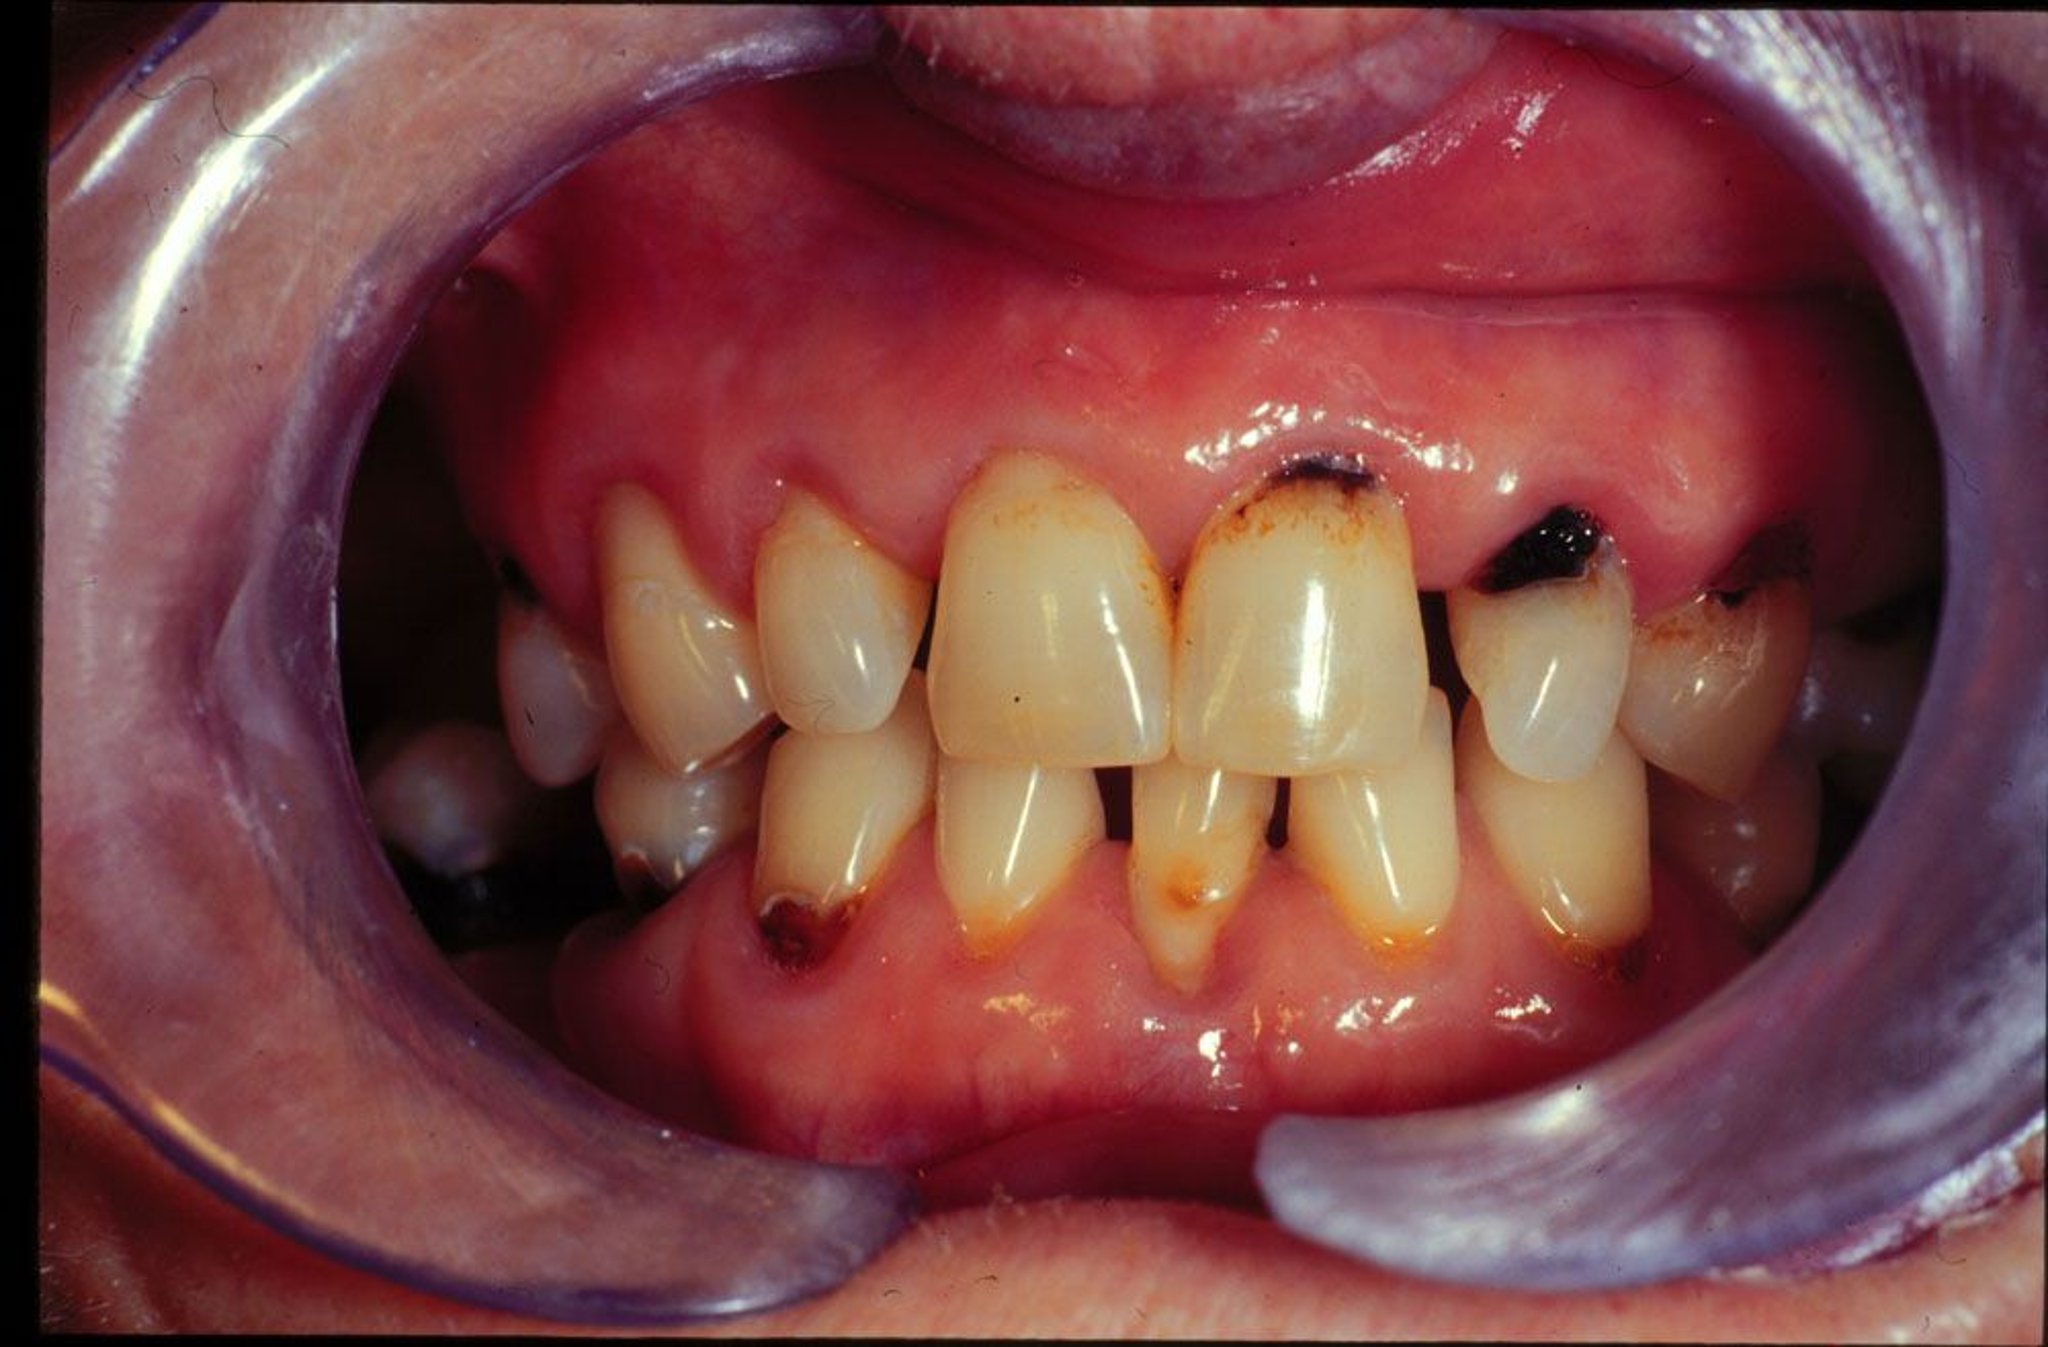

Caries dental nueva y recidivante en un paciente con xerostomía.

Image provided by Jonathan A. Ship, DMD.